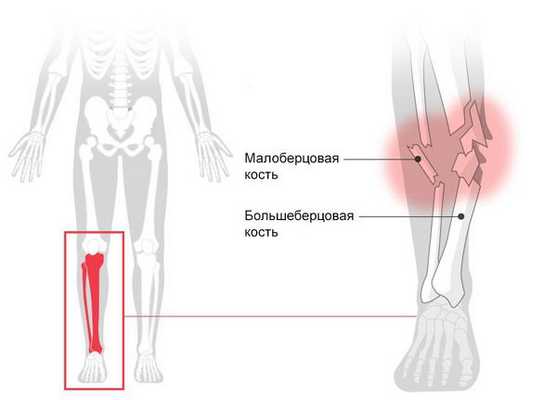

Голень - часть скелета между бедром и стопой, состоящая из двух трубчатых костей (большеберцовой и малоберцовой). Основную нагрузку несет на себе более крупная большеберцовая кость. Мыщелки (выступы в верхней части большеберцовой кости) соединяются с бедренной костью, образуя нижнюю суставную поверхность коленного сустава. Своей нижней частью большеберцовая кость сочленяется с таранной костью, образуя голеностопный сустав.

Малоберцовая кость располагается с наружной стороны, увеличивает стабильность и прочность голени. Обе кости голени соединяются между собой (вверху - при помощи общего сочленения, в средней части - посредством межкостной мембраны, внизу - при помощи связок). На нижних концах обеих костей голени имеются выступы (лодыжки), которые с двух сторон охватывают голеностопный сустав и придают ему поперечную стабильность.